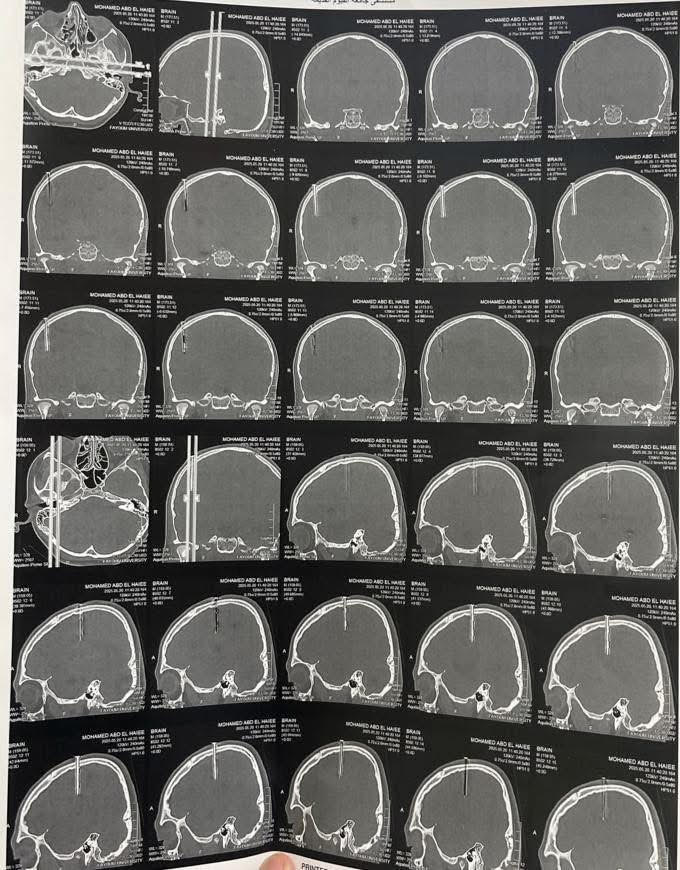

استخراج مسمار معدني اخترق عظام جمجمة لطفل 11 عاماً

أجرى أطباء جراحة المخ والأعصاب بمستشفيات جامعة الفيوم، جراحة دقيقة ومعقدة لاستخراج جسم معدنى" مسمار " 10 سم اخترق عظام جمجمة طفل يبلغ من العمر ١١ عامًا، دون أن يمتد إلى أنسجة المخ الحيوية، من جهته أشاد الدكتور ياسر مجدى حتاته رئيس جامعة الفيوم، بجهود الفريق الجراحى، وقال إن الجراحة كانت دقيقة وخطيرة ومعقدة وكللت جهودهم بالنجاح، وعكست كفاءة الطاقم الطبي والتمريضي في التعامل مع الإصابات الدقيقة والمعقدة.

أضاف الدكتور محمد صفاء مدير المستشفيات الجامعية بالمحافظة، ان الطفل المصاب وصل إلى قسم الطوارئ بحالة سيئة وكان يعاني من وجود جسم غريب ظاهر في فروة الرأس، وتبين من خلال الفحص الإكلينيكي وأشعة الـ CT وجود مسمار معدني أخترق بزاوية رأسية العظام الجدارية الأمامية للجمجمة، ممتداً بعمق نحو القشرة الدماغية، الأمر الذى شكل خطورة بالغة على حياة الطفل واستدعى تدخّل فريق جراحة المخ والأعصاب بمستشفيات جامعة الفيوم .

موضحاً أنه تم تحضير الحالة على الفور للعمليات، و تم إجراء فتح جراحي دقيق حول الجسم المعدني، وتم استئصال جزء عظمي يحتوي على المسمار لتجنب أي إصابة إضافية للمخ أو الأوعية الدموية المجاورة، و ان الجراحة تمت بنجاح ودون أي مضاعفات و الحالة الصحية والطبية للطفل حالياً مستقرة، مؤكداً ان الحالة التى تعامل معها الفريق الجراحى تعد من الحالات النادرة التي تم توثيقها، و أكدت كفاءة الفريق الجراحى والتمريضي في التعامل مع الإصابات الدقيقة والمعقدة بمستشفيات جامعة الفيوم .